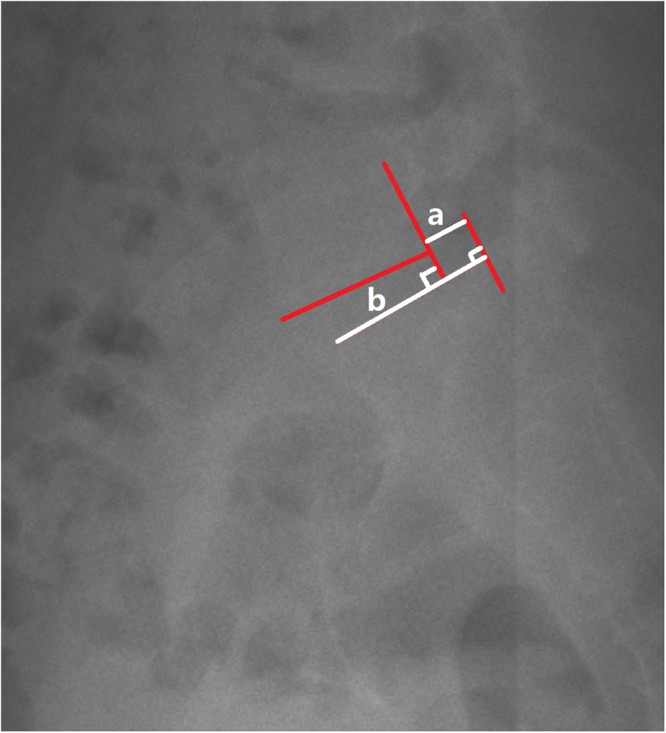

Slip percentage was assessed in those lumbar isthmic spondylolisthesis patients32. Figure 4 demonstrated the measurement of slip percentage.

Figure 4.

Demonstrated the measurement of slip percentage.